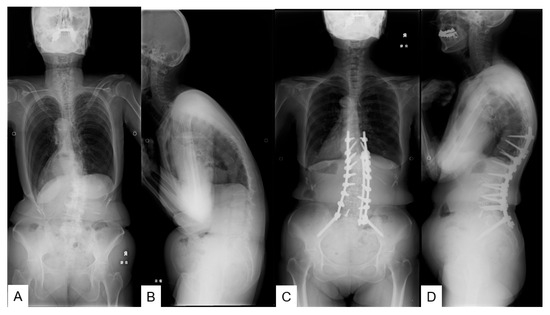

:1. Introduction

2. Materials and Methods

2.1. Patient Demographics